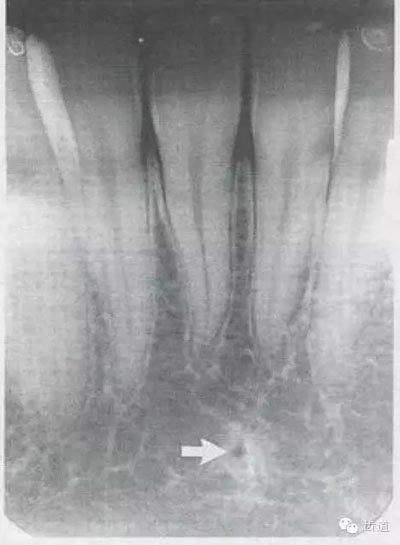

2)營(yíng)養(yǎng)管:

常見(jiàn)于下頜前牙區(qū),在牙根之間的牙槽骨內(nèi)并與牙長(zhǎng)軸平行的密度低的條狀影像。此為小血管進(jìn)入牙槽突的影像。